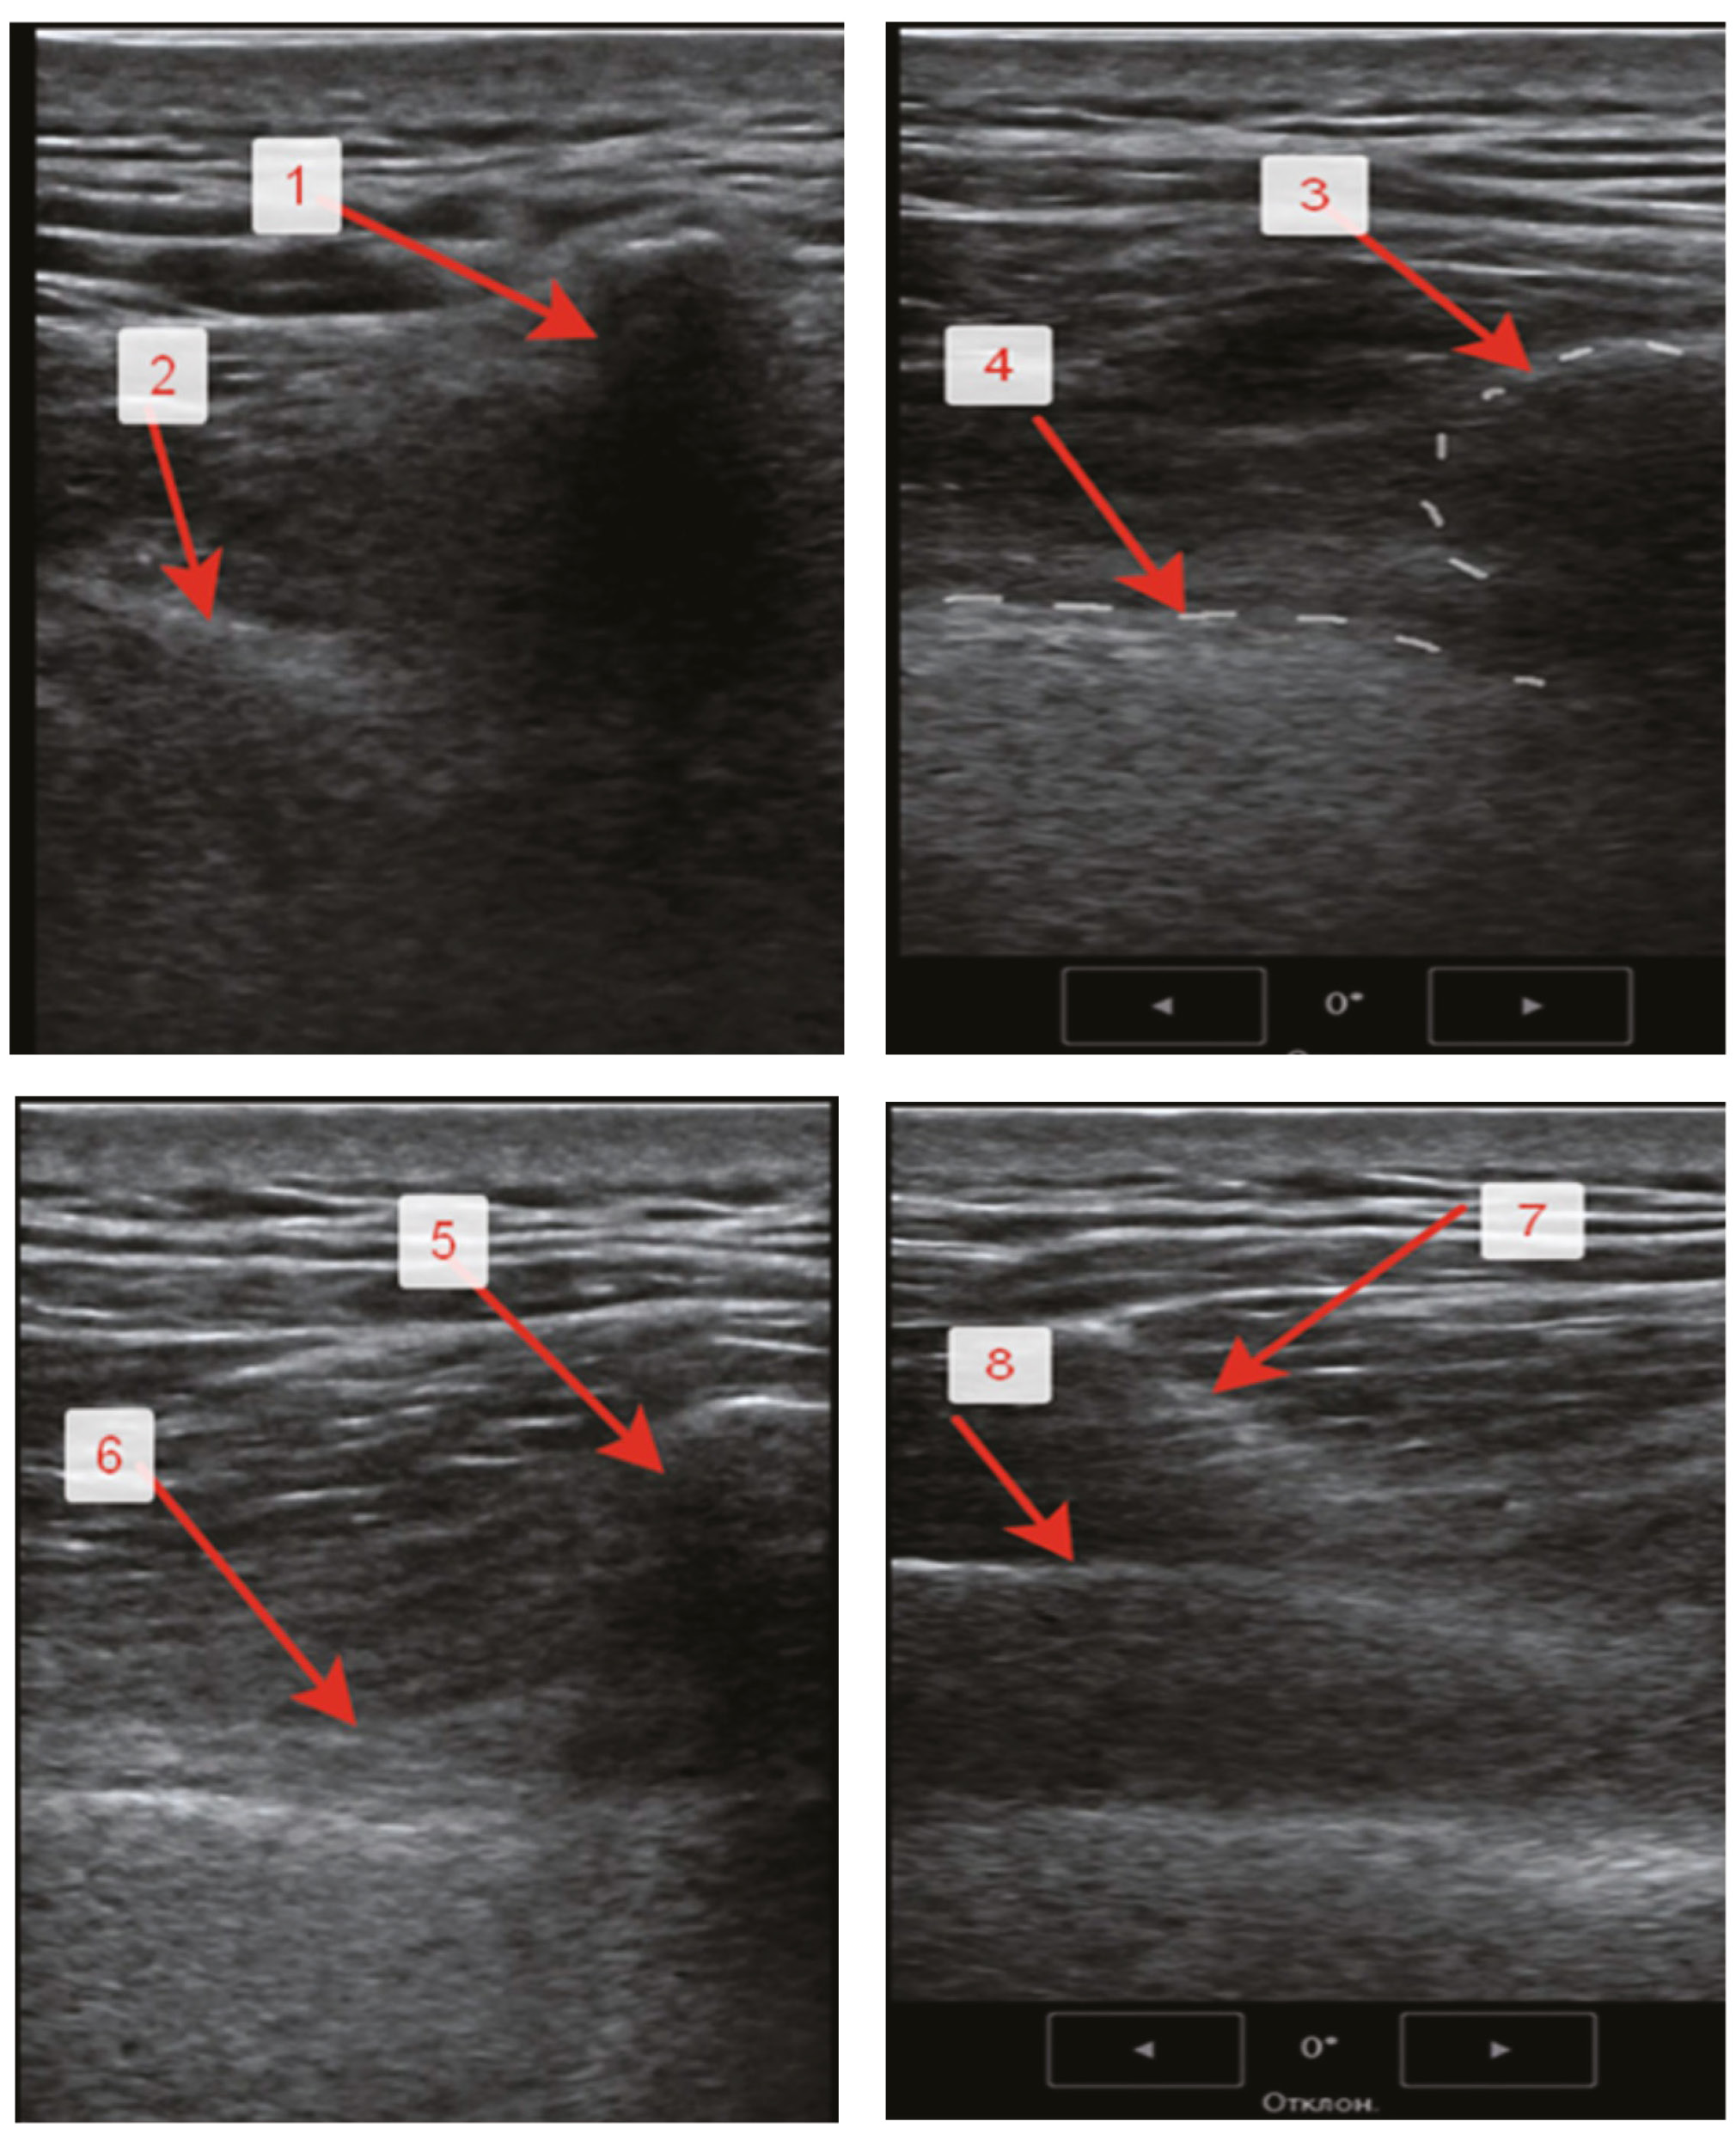

ПВБ в группе 1 выполняли на стороне операции в условиях ОА в положении пациента лёжа на боку с использованием линейного датчика аппарата экспертного класса «Mindray UMT-400» с рабочей частотой 6–10 Мгц (Medeq, Китай). Датчик выводили в «косое» положение, что позволяло визуализировать плевру, ограничивающую паравертебральное пространство (ПВП) спереди, рёберно-позвоночную связку, ограничивающую его сзади, и медиально-рёберно-позвоночное сочленение. ПВП представлялось в форме гипоэхогенного треугольника. Для пункции и катетеризации ПВП использовали набор для продлённой ЭА B. Braun. Пункцию осуществляли на уровне ThVII–ThVIII. Правильное положение иглы определялось характерным вентральным смещением плевры. На рис. 1 представлена ультразвуковая (УЗ) картина верификации и пункции ПВП.

Рис. 1. Ультразвуковая картина верификации и пункции паравертебрального пространства. Примечание. 1 — тень остистого отростка позвонка, 2 — поперечный отросток, 3 — рёберно-позвоночное сочленение, 4 — париетальная плевра, 5 — рёберно-позвоночное сочленение, 6 — паравертебральное пространство, 7 — игла по продольной оси сканирования, 8 — вентральное движение плевры. / Fig. 1. Ultrasound picture of paravertebral space verification and puncture. Note. 1 — the shadow of the spinous process of the vertebra, 2 — transverse process, 3 — costal-vertebral articulation, 4 — parietal pleura, 5 — costal-vertebral articulation, 6 — paravertebral space, 7 — needle along the longitudinal axis of scanning, 8 — ventral pleural movement.